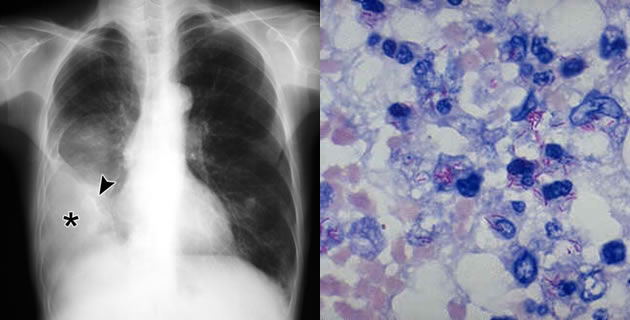

U dijagnozi TBC pleurita treba računati na anamnezu, ali se fizikalni nalaz bitno ne razlikuje od bilo kod pleuralnog izliva. Izgled tečnosti se razlikuje od izliva druge etiologije:

Mikroskopskim pregledom sedimenta ili kulturom, mycobacterium tuberculosis se otkrije u 50% slučajeva. Pri pleuralnoj punkciji, neki kliničari uzimaju i bioptički materijal pluća (uzorak). Ponavljanje torakocenteze i drenaže kod TBC pleuritisa je kontraindicirano. Međutim, kod tuberkulin negativne djece treba test ponoviti za dvije do tri sedmice.